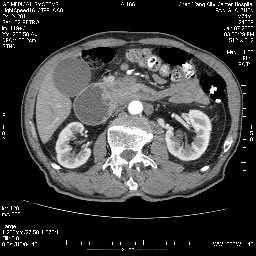

女,74岁,呕吐10余日

考虑来源于十二指肠水平段的恶性占位,侵及周围组织,特别是胰腺,可见区域淋巴结肿大,左侧下腔静脉畸形。

十二指肠水平段腔内占位伴梗阻,中等度较为均匀的强化,洗脱慢,区域淋巴结显示增多,符合腺癌表现。下腔静脉变异。

十二指肠降段扩张,水平段狭窄成鼠尾状,肠壁明显增厚,胰腺勾突增大成不均匀强化,其内可见低密度区,胆囊增大,1十二指肠水平段腺癌侵犯胰腺勾突可能大,2胰腺癌侵犯十二指肠(只有胆囊增大没有肝内外胆管扩张不好解释)代除外.

十二指肠降段扩张,水平段狭窄成鼠尾状,肠壁明显增厚,胰腺勾突增大成不均匀强化,其内可见低密度区,胆囊增大,1十二指肠水平段腺癌侵犯胰腺勾突可能大,2胰腺癌侵犯十二指肠 。

今日手术结果:胰腺钩突癌侵犯十二直肠,腹腔淋巴结转移.